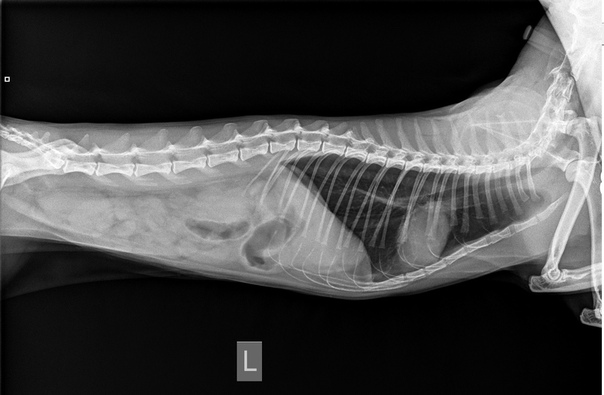

- Рентгенография – позволяет рассмотреть петли тонкого кишечника, располагающиеся в центральной зоне брюшной полости в двух проекциях – вентродорсальная и боковая. Аномальное расширение исследуемого материала сигнализирует о растяжении от постороннего предмета или от иных причин. На снимке можно обнаружить металлические вещи, кости, камни, стекло. Впрочем, не всегда инородные тела видны с помощью рентгенографии. Так, сложно обнаружить на снимке нитки, резиновые изделия, полиэтилен или тряпку. В этом случае применяют контрастную рентгенографию или другие способы исследования.

При первичном осмотре мы обнаружили умеренную абдоминальную болезненность и обезвоживание 3-4%. Общее состояние было удовлетворительным. Но на рентгенограммах были признаки нанизывания кишечника на линейное инородное тело.

Ваш ветеринар может порекомендовать рентген брюшной полости, чтобы лучше понять, что происходит в брюшной полости. Они будут искать инородное тело, а также обнаруживать изменения в газовой структуре кишечника (что указывает на закупорку).

Рекомендации теста могут включать: - Рентгенограммы брюшной полости (рентгеновские снимки) — важный тест. К сожалению, не все инородные материалы видны на первоначальном рентгеновском снимке. Иногда рекомендуется добавление красителя, такого как барий, чтобы определить наличие инородного тела или непроходимости желудка.

Рентгенограммы (рентгеновские снимки) были сделаны для оценки его живота.

Твердый объект располагался в кишечнике в каудальном левом квадранте брюшной полости.Поскольку он перекрывал толстую кишку, не сразу было очевидно, находится ли объект в тонком или в толстом кишечнике. Мы провели ультразвуковое исследование его брюшной полости и обнаружили объект в тонкой кишке, на полпути между желудком и толстой кишкой.

При подозрении на инородное тело рентгенограммы (рентгеновские снимки) часто являются первым рекомендуемым тестом. В случае подозрения на инородное тело пищевода, скорее всего, будет рекомендована рентгенография грудной клетки. Если есть подозрение на инородное тело в желудке или тонком кишечнике, будет рекомендована рентгенограмма брюшной полости. УЗИ брюшной полости часто используется, чтобы определить, какая часть кишечного тракта задействована, чтобы спланировать терапию.